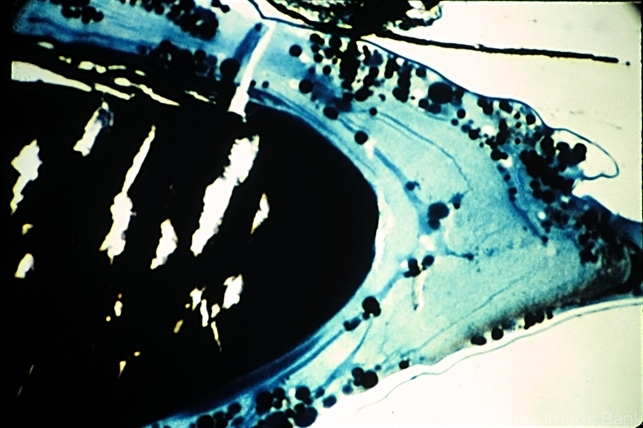

- senile cataract, hypermature lens

- Senile cataract (trichrome stain x 16). A hypermature lens is shown with a dense nucleus, an almost liquified cortex, and a wrinkled capsule. Some of the fluid has been lost (Scheie Eye Institute, No. 1596.)